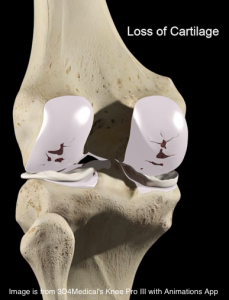

La artrosis es una enfermedad degenerativa que afecta eminentemente al cartílago articular, envejeciéndolo y, finalmente destruyéndolo. La pérdida del cartílago articular es lenta, progresiva y se hace de una manera parcheada. Me gusta usar el símil de un green de golf, de una pradera de césped. Cuando se riega poco es césped, van apareciendo «parches» de hierba seca que progresivamente van superponiéndose hasta terminar de secar esa agradable y confortable pradera. El cartílago también va «secándose» de manera parcheada hasta que finalmente se pierde de la superficie articular casi en su totalidad. Como se puede ver en la secuencia de ilustraciones, su eliminación final tiene consecuencias muy directas en la función de la articulación, ya que ésta finalmente pierde este excepcional «tapiz» viscoelástico que contribuye a paliar la fricción y el desgaste entre 2 huesos que íntimamente se contactan y articulan. Al desaparecer la lubricación, la fricción aumenta y las articulaciones «chirrían» como las bisagras envejecidas traduciéndose en dolor, rigidez, inflamación, deformidad y limitación del movimiento.

Artrosis vs Artritis: en la artrosis el cartílago finalmente se pierde y los huesos friccionan entre sí